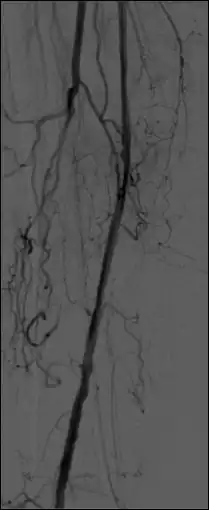

- A second variation on the theme involves acquiring images of both the arterial and the venous vessels in the same region of the patient (e.g. the carotid arteries and jugular veins in the neck) so that when a mask image in the arterial phase is subtracted from a live image from the venous phase, a subtracted image showing both arterial and venous vessels can be generated. A third variation is referred to as Roadmapping - see Figure 7.7 - where an image at peak opacification is used as a mask and subsequent subtraction images, without injection of additional contrast medium, are used to guide advancement of a catheter or guide-wire.

- Additional processes involve Bolus Chasing, Rotational Angiography and Volume Tomographic Angiography. Bolus Chasing[28] has been found to be particularly helpful in peripheral angiography, for example. Here, the progress of the contrast medium is tracked automatically and used to increment the table and/or XRT/image receptor movement to the next anatomical region. The subsequent set of subtraction images can then be used to construct a composite image of the peripheral vasculature. In Rotational Angiography[29], a C-arm assembly, for example, can be caused to rotate at 10 - 30 degrees per second during the imaging sequence. Subsequent dynamic display of the subtraction images can be used to generate a perceived 3D presentation so that complex relationships within the vasculature can be more readily appreciated. Volume Tomographic Angiography[30] is similar to Computed Tomography (CT) where the C-arm is rotated around the patient during the imaging sequence. The image data is subject to a volume reconstruction algorithm which permits generation of three-dimensional images of the opacified vasculature. We will consider this latter process in more detail below.